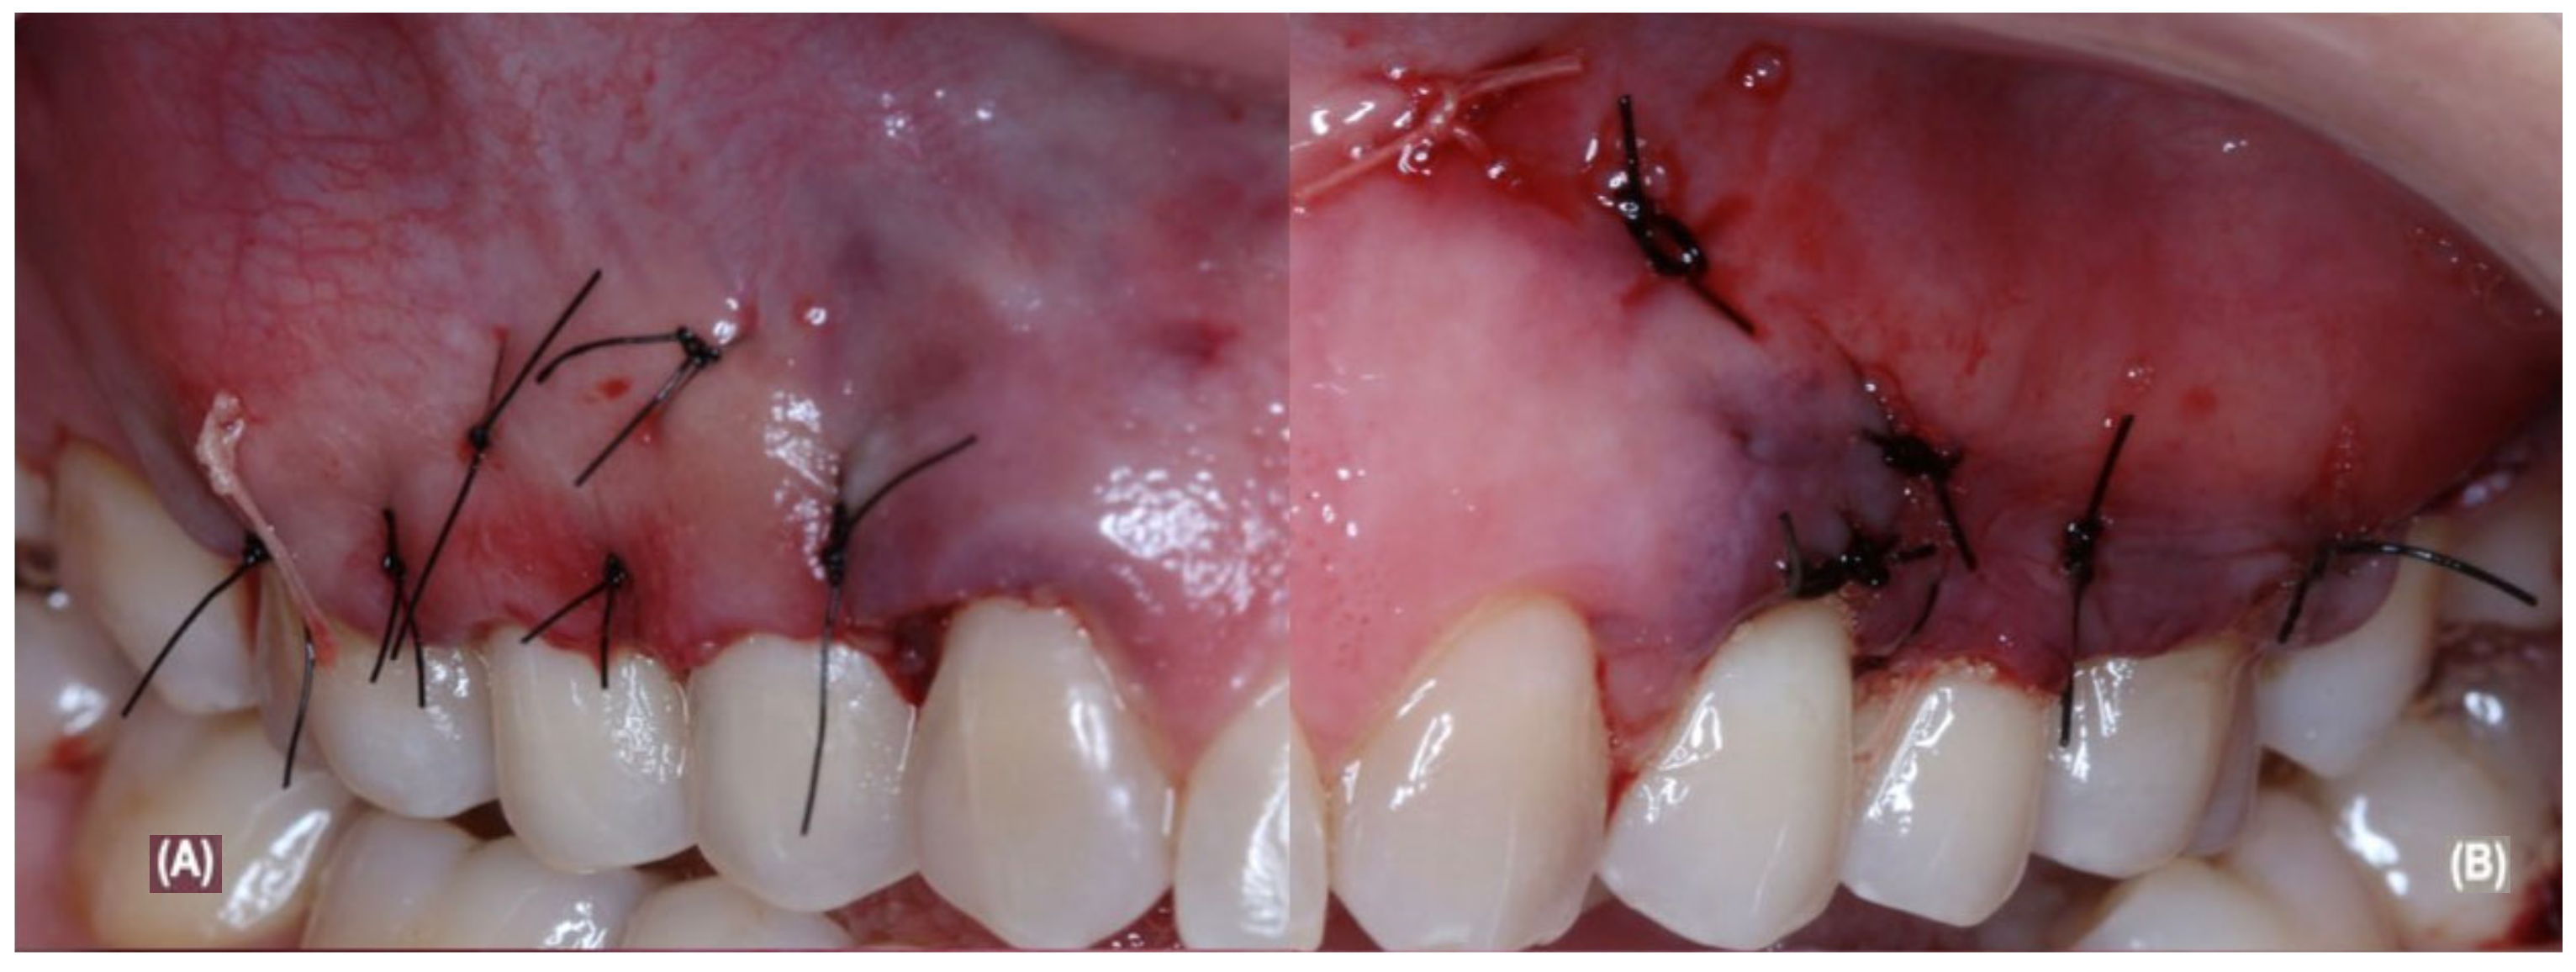

2.5. Periodontal Surgical and Post-Operative Treatment